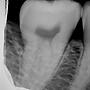

Re: [問題] 牙冠增長術或未來植牙的問題

[ teeth_salon ]4 留言, 推噓總分: +1